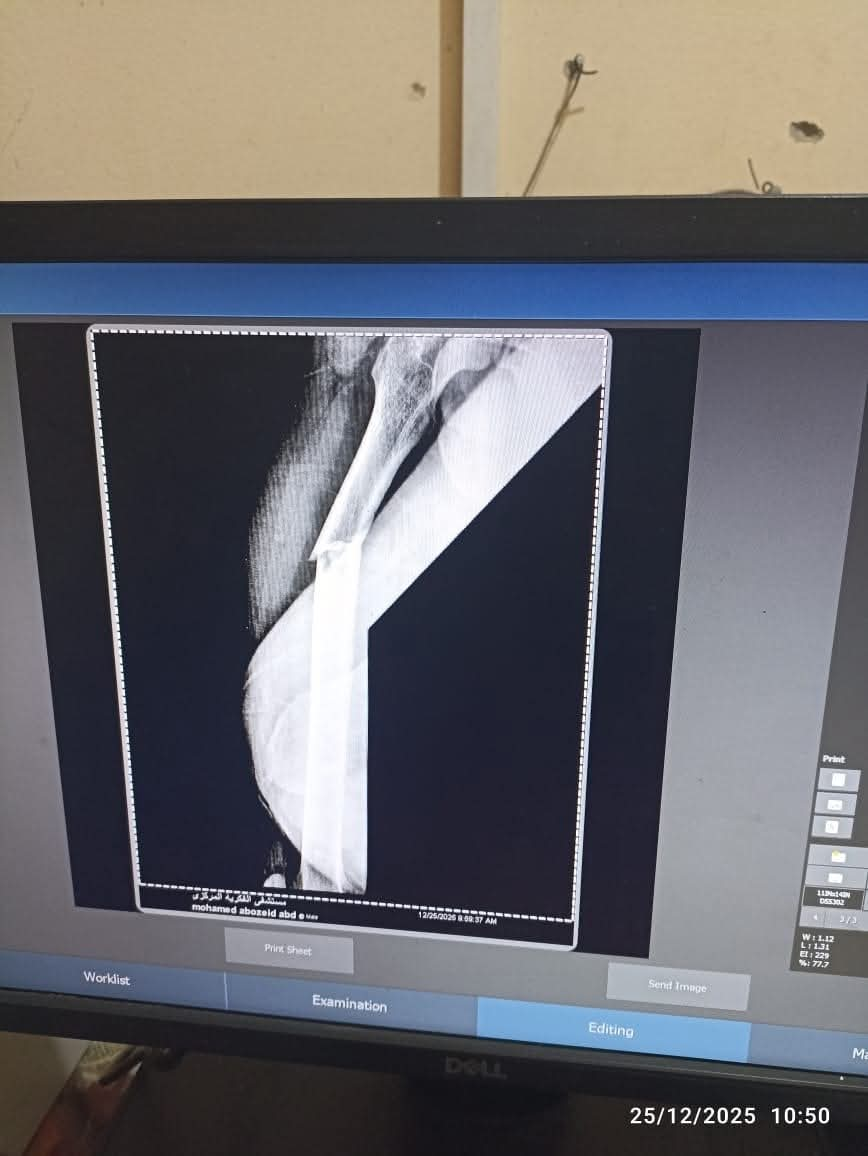

قرر الفريق الطبي استخدام تقنية المسمار النخاعي التشابكي (Interlocking Nail)، وهي من أحدث الطرق العالمية في علاج كسور العظام الطويلة، حيث توفر استقراراً فورياً للكسر، وتسمح للمريض بالبدء في التماثل للشفاء والحركة في وقت قصير جداً مقارنة بالطرق التقليدية.

خرج الشاب من غرفة العمليات بحالة مستقرة بفضل الله، وهو الآن تحت الملاحظة الطبية الدقيقة لاستكمال البرنامج العلاجي، وسط سعادة غامرة من ذويه وتقدير لإدارة المستشفى والطاقم الطبي على سرعة الاستجابة والمهارة الفائقة.